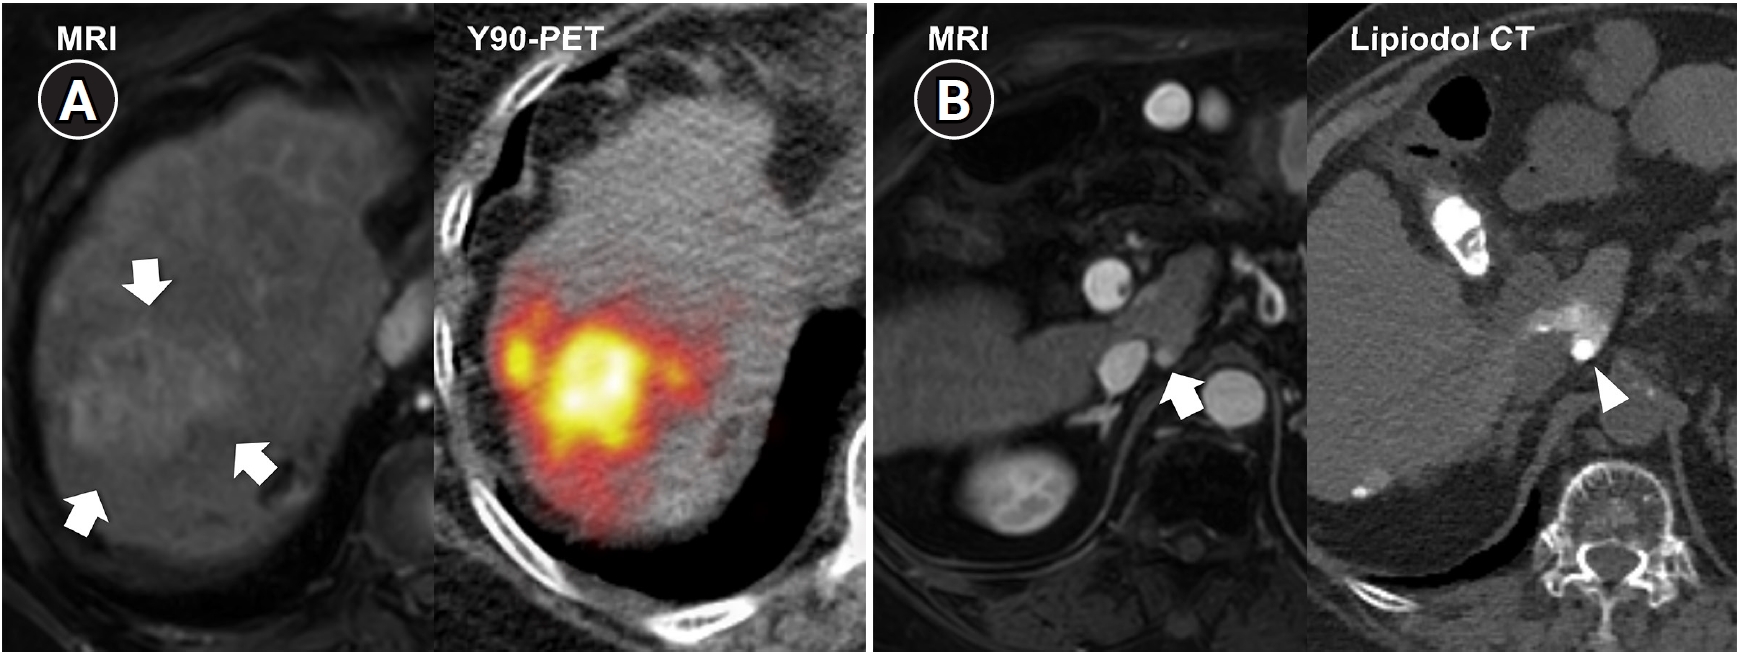

Fig. 3.

Central bile duct injury after transarterial radioembolization in an 80-year-old woman with ruptured hepatocellular carcinoma. (A) Computed tomography obtained 5 months after selective infusion of Y-90 microspheres via A1, A4, and A8 shows extensive radiation necrosis (arrows) in segments 4 and 8, with dilatation of the intrahepatic bile ducts (circle) in the left lateral segments. (B) Because of progressive jaundice and pruritus, percutaneous transhepatic biliary drainage was performed, and cholangiography showed segmental occlusion of the left main bile duct (arrow), suggesting radiation-induced ductal injury.

Fig. 3. Central bile duct injury after transarterial radioembolization in an 80-year-old woman with ruptured hepatocellular carcinoma. (A) Computed tomography obtained 5 months after selective infusion of Y-90 microspheres via A1, A4, and A8 shows extensive radiation necrosis (arrows) in segments 4 and 8, with dilatation of the intrahepatic bile ducts (circle) in the left lateral segments. (B) Because of progressive jaundice and pruritus, percutaneous transhepatic biliary drainage was performed, and cholangiography showed segmental occlusion of the left main bile duct (arrow), suggesting radiation-induced ductal injury.